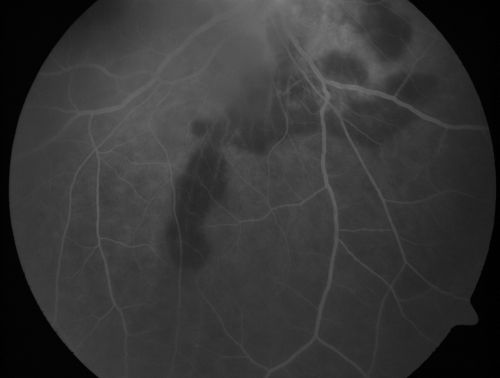

Serpiginouse Choroiditis (Chorioretinitis) - Acute Right Eye - Old Left Eye VA 20/25 OD , 20/50 OS

63-year-old woman has serpiginous choroiditis (date - March 2011).  The right eye has not been previously involved, and then she noticed new onset floaters in the right eye for the last two weeks.  Her vision in the right eye is hazy because of that.

VISUAL ACUITY:  Vision OD is 20/25, OS is 20/50